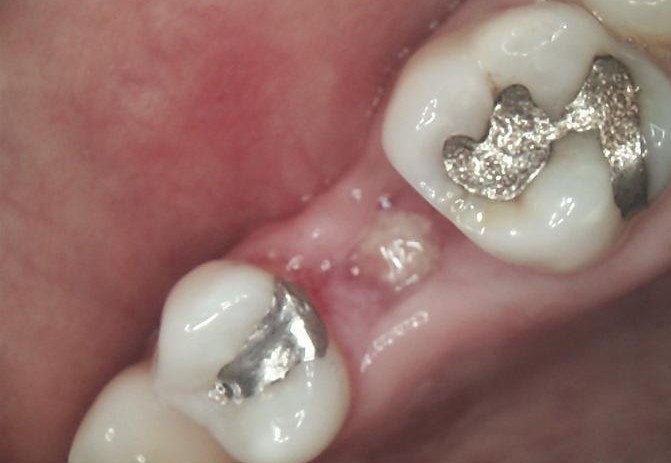

SURGERY

The failed implant was atraumatically removed, followed by thorough debridement of the surgical site.

Bone graft material was placed to restore adequate bone volume and support future implant placement.

A new implant was inserted in a prosthetically driven position, ensuring primary stability.

Surgical site was sutured to allow uneventful healing.